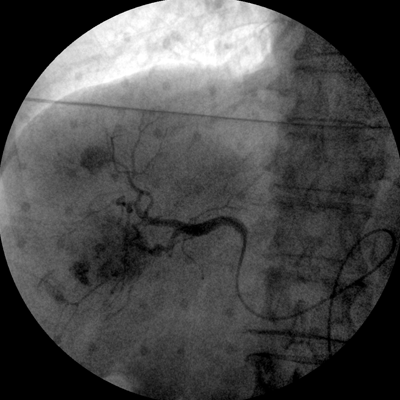

智能化控制系統(tǒng), 讓手術(shù)高效暢捷

四維電動(dòng)運(yùn)動(dòng)控制,平滑定位,使得復(fù)雜角度快速實(shí)現(xiàn)。

專業(yè)的圖像處理系統(tǒng),為您提供高分辨率、高灰階圖像。